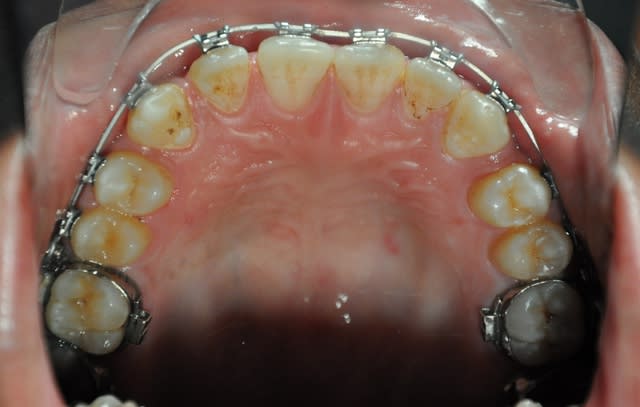

2ème étape

3ème étape,déjà postée